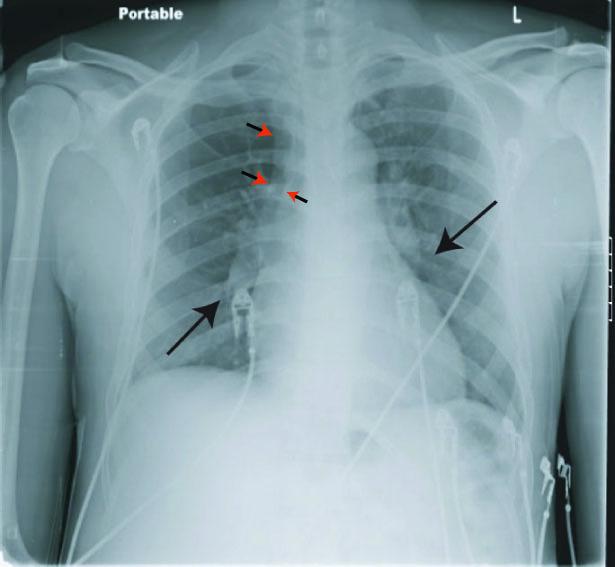

Pulmonary embolism (PE) is a life-threatening condition that may present as dyspnea, chest pain, cough or hemoptysis, but often occurs without symptoms. It is not typically associated with hiccups. Hiccups are generally self-limiting benign contractions of the diaphragm that may be associated with medications or food but may also be symptomatic of serious disease when persistent. We report 3 cases of PE presenting as persistent hiccups.

肺栓塞(PE)是一种危及生命的疾病,可能表现为呼吸困难、胸痛、咳嗽或咯血,但常无症状。它通常与打嗝无关。打嗝通常是膈肌的自限性良性收缩,可能与药物或食物有关,但当持续存在时也可能是严重疾病的症状。我们报告了 3 例以持续打嗝为表现的 PE。